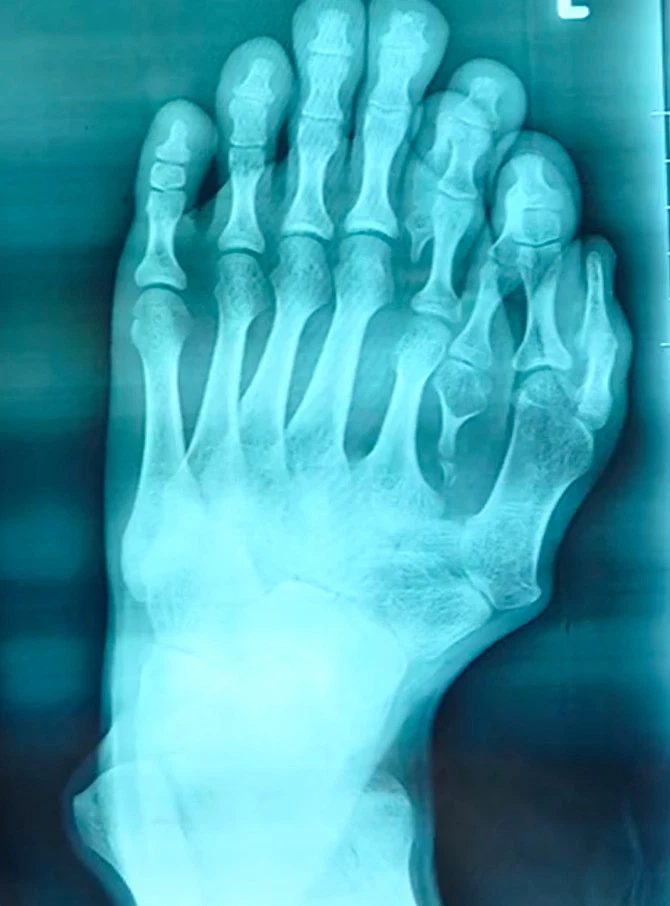

Bàn chân được chụp X-quang